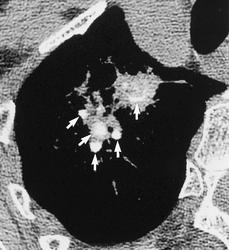

Лучевая диагностика туберкулеза сегодня

Я.В. Лазарева, Г.В. Ратобыльский, Е.В. Серова, М.Б. Мальсагов

НИИ фтизиопульмонологиии ММА им. И.М. Сеченова